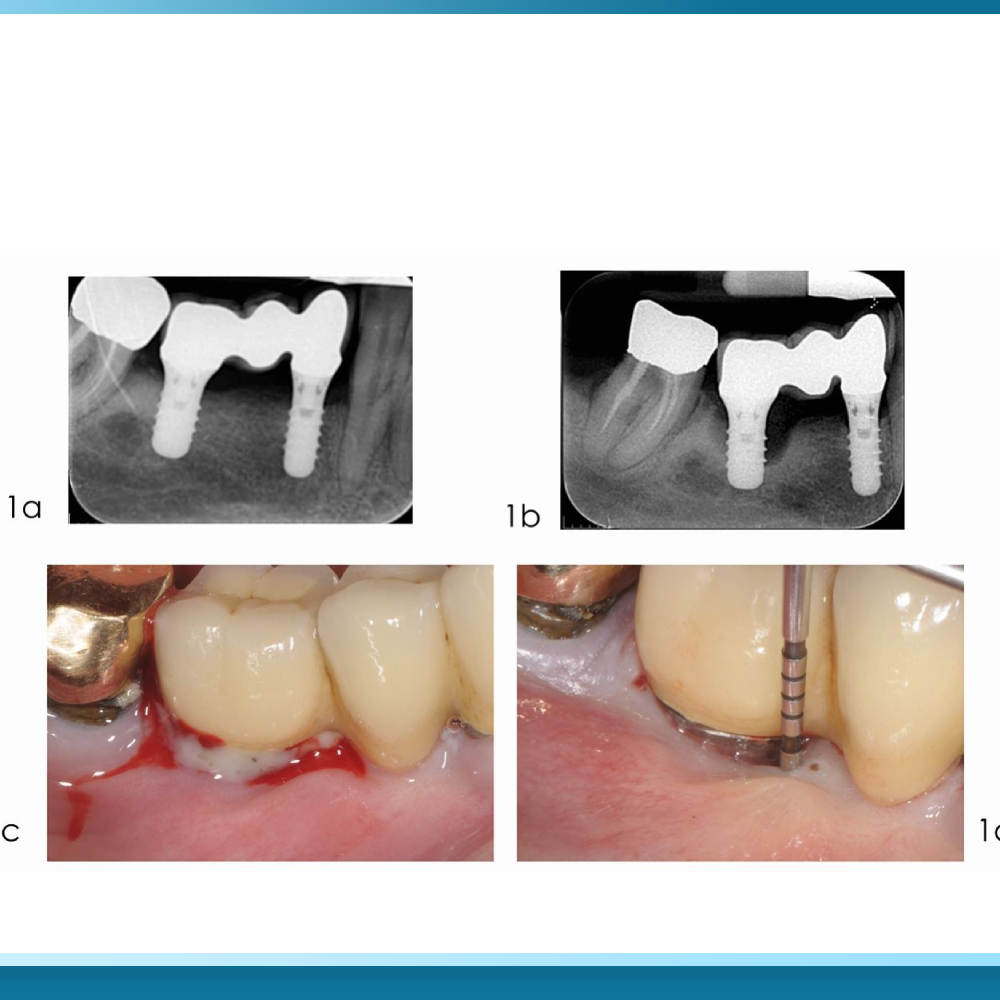

Việc duy trì thói quen sử dụng chất kích thích không kiểm soát sau khi trồng răng All on 6 dẫn đến hậu quả nghiêm trọng nhất là viêm quanh Implant (Peri-implantitis). Đây là tình trạng nhiễm trùng mạn tính ảnh hưởng đến cả mô mềm và mô xương nâng đỡ trụ.

Dưới tác động của rượu bia và thuốc lá, phản ứng viêm diễn ra dữ dội hơn, khiến túi nướu xung quanh Implant bị sâu dần, mủ xuất hiện và xương hàm bị tiêu biến nhanh chóng. Nếu không được can thiệp kịp thời, sáu trụ Implant sẽ mất dần điểm tựa cơ học, dẫn đến hiện tượng lung lay và buộc phải phẫu thuật tháo bỏ toàn bộ hàm sứ cùng các trụ đã cấy ghép.

Dấu hiệu cảnh báo sớm mà người bệnh cần lưu ý bao gồm: nướu sưng đỏ, chảy máu khi vệ sinh, có mùi hôi lạ từ vùng trụ hoặc cảm giác hàm bập bênh khi nhai. Các triệu chứng này thường tiến triển âm thầm nhưng tàn phá cấu trúc xương hàm một cách triệt để nếu các yếu tố kích thích từ rượu bia và thuốc lá vẫn tiếp tục tồn tại.